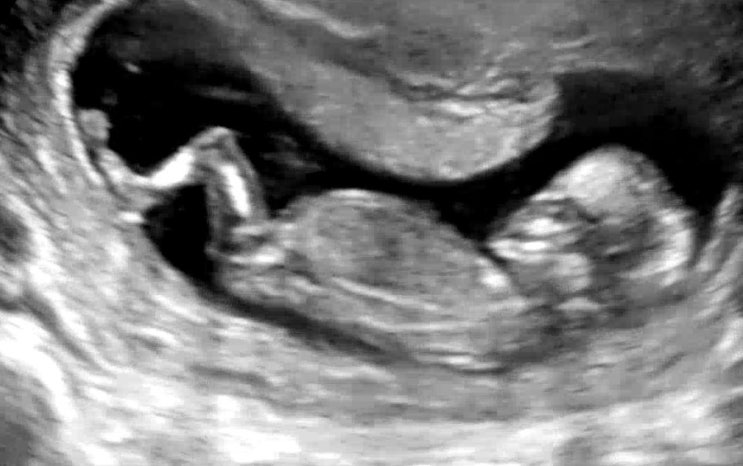

13주6일 두 번째 성별힌트

약 열흘만에 행복이를 보고 왔다.ㅎㅎ 하이베베로 행복이가 잘 있는지를 매일 확인했었는데 14주차쯤 되면 ...